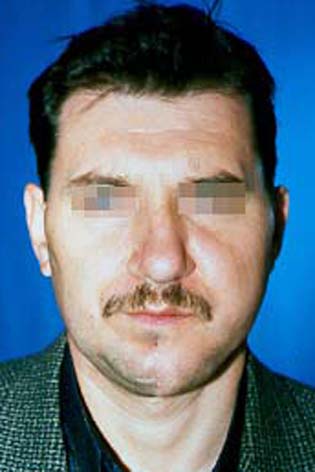

Пациент със злокачествен тумор на дясната част на долната челюст, наложил резекцията й. Възстановена е 1 година по-късно, традиционно чрез собствена костна тъкан от хълбочния гребен - случай на доц. Джоров.

Пациент с тежка травматична деформация на дясната орбита, реконструирана с костни присадки от черепния свод – случай на доц. Джоров.